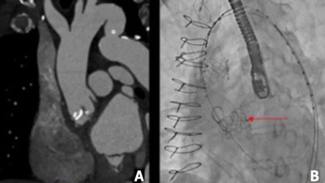

A 65-year-old man who presented with lateral ST-segment-elevation myocardial infarction was referred for primary percutaneous coronary intervention. These image show brachiocephalic artery perforation with subsequent mediastinal hematoma.